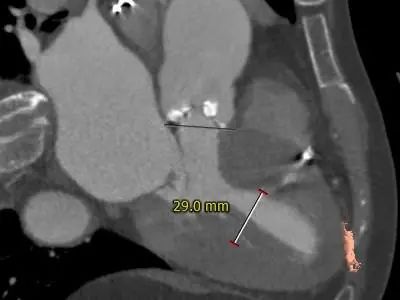

2021年12月4日,郑州市第七人民医院赵育洁主任、张申伟主任团队成功完成TaurusElite®可回收经导管主动脉瓣系统首例植入。此病例十分典型,Type 0型二叶式主动脉瓣,重度钙化主要沿两窦瓣叶边缘连续分布,瓣叶增厚,窦内少量钙化向窦底延伸至瓣环水平,瓣环水平夹角54接近横位心,升主动脉严重扭曲。术后瓣膜工作正常稳定,未出现冠脉阻挡和瓣周漏等情况,血流动力学均得到有效改善,为患者带来更长久生存期受益和更高生活质量。

患者:女性,71岁,以间断胸闷气短4年为主诉入院,术前诊断:1.冠心病2.高血压病2级3.主动脉瓣重度狭窄二尖瓣重度关闭不全4.心律失常,三度房室传导阻滞。术前峰值跨瓣压差 120mmHg,瓣上速度 4.5m/s,瓣口面积0.8cm²。

1.Type 0 型二叶瓣,瓣叶增厚,双侧瓣叶边缘连续条状钙化,瓣膜锚定难度适中,瓣膜植入受两侧钙化挤压存在移位风险及瓣周漏风险。

主动脉根部测量